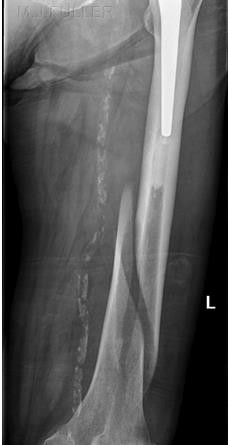

- Phẫu thuật:

- Nẹp vít (AO)

- Đinh nội tủy

- Buộc chỉ thép, xuyên đinh

- Ghép xương

Ưu điểm của phẫu thuật là cho phép nắn xương đúng vị trí, bất động tương đối chắc chắn, tránh được di lệch thứ phát, người bệnh có thể tập cử động và chịu trọng lượng sớm, tránh các biến chứng teo cơ, cứng khớp, loãng xương.